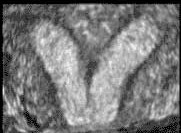

שני מומי הרחם הנפוצים ביותר בנשים עם הפלות חוזרות הם הרחם עם המחיצה (Septated uterus) המהוים כ- 35% מן המומים ורחם דו קרני - (Bicornuate uterus) המהוים כ– 40% מן המומים.

רחם עם מחיצה הוא רחם שבחללו קיימת מחיצה המחלקת אותו לשני חלקים (או קרניים). גודלה של המחיצה יכול לנוע ממחיצה חלקית ועד למחיצה מלאה. המחיצה, שניתן לדמיינה כמעין עמוד היורד מתקרתו של אולם, בנויה מרקמה השונה בהרכבה משריר הרחם ואשר אספקת הדם אליה אינה עשירה כאספקת הדם לשריר הרחם ולכן, עובר אשר נקלט ומשתרש באיזור המחיצה סיכויו לשרוד קטנים יותר. הטיפול במקרים אלה הוא הסרת המחיצה על מנת לשפר את סיכויי העובר להשתרש רק באיזורים בהם צפויה השתרשות אופטימלית יותר.

רחם דו קרני הוא רחם אשר מורכב למעשה משני רחמים וכל רחם כזה הוא "קרן". בשלב מוקדם מאד בחיים העובריים הרחם הנורמלי נוצר מהתאחדות שני צינורות שריריים הנקראים צינורות מילריאניים (Mullerian ducts). בנקודת המפגש שלהם נספג הדופן המשותף שלהם במלואו וכך נוצר חלל רחם אחד. ברחם דו קרני, תהליך זה אינו מתקיים, בדרגות שונות, ונוצר רחם עם שתי קרניים כמו אוזני ארנב. לרחם כזה גם כן שני חללים כמו ברחם המחיצתי אבל החלק האמצעי בנוי מרקמת שריר תקינה. מנגנון ההפלה ברחמים כאלה אינו על רקע יכולת השתרשות לקויה, כמו ברחם מחיצתי, אלא במנגנון אחר שאינו ברור די צורכו וקשור יותר לאי ספיקה של צואר הרחם. ברחם כזה ההפלות מאוחרות יותר ומתחילות בהתרחבות צואר הרחם בפקיעת קרומים ובירידת מים. הפרוגנוזה (הסיכוי להריון תקין) במקרה של רחם דו קרני טובה מזו של רחם עם מחיצה ואינה דורשת תיקון כירורגי כפי שהיה בשנים עברו.

הכלי הזמין ביותר לאבחון מומי רחם או שרירנים הוא האולטרה-סאונד. בעזרתו ניתן להעריך את מבנה הרחם, האם הוא דו קרני או מחיצתי והאם ישנם שרירנים המעוותים בצורה משמעותית את חלל הרחם. אולטרה-סאונד תלת ממדי נותן כלי נוסף להערכה זו.